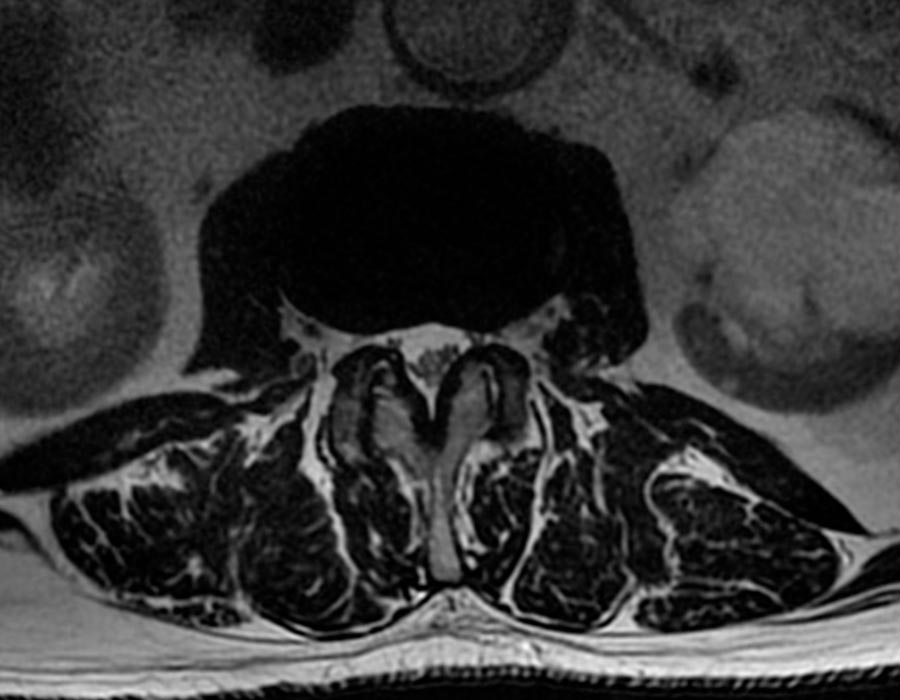

estenosis de canal radiografia

Cirugia de columna para estenosis de canal

Vision transversal columna vertebral operacion